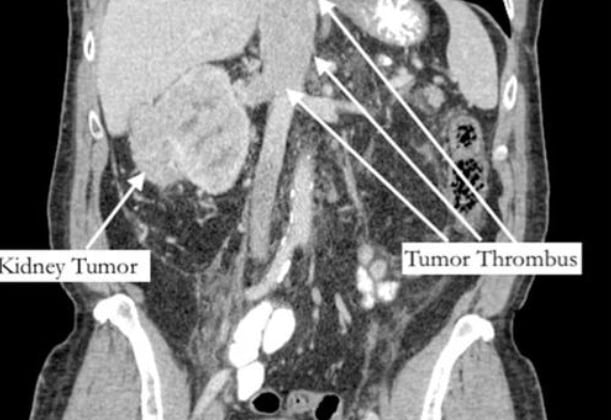

Tras una exploración abdominal, fue diagnosticado con cáncer de riñón y un trombo tumoral que creció a través de la vena renal y tapaba la vena cava, principal vena que drena al corazón.

Por fortuna, una cirugía de 12 horas, un tumor de 1,3 kilos extirpado y un bypass coronario revirtieron el que habría sido un fatal destino, concediéndole una segunda oportunidad.

Con respecto al dolor de pie, la vena cava estaba obstruida y esto generaba presión en sus extremidades inferiores, pero como los síntomas del cáncer de riñón pueden ser muy vagos, fue complicado encontrarlo.